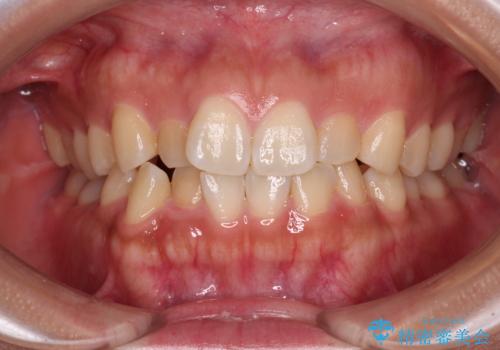

捻れて前に出ている前歯 ワイヤー装置での非抜歯矯正